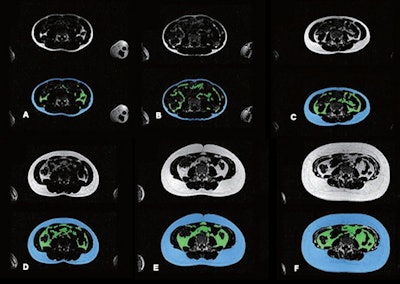

Example results show automated abdominal adipose tissue segmentation into SAT and VAT using Dixon MRI acquisitions in different children. In each image, top and bottom images represent fat-only images without (top) and with (bottom) segmentation. Blue areas denote SAT, and green area denotes VAT. Images A-F represent six children with varying body sizes and varying amounts of abdominal SAT and VAT. Images courtesy of ARRS.The team also reported that the two observers assigned a score of 3, the best possible visual score, for SAT in 94% and 93% for undersegmentation proportion, and 99% and 99% for oversegmentation proportion. The observers also assigned a score of 3 for VAT in 99% and 99% for undersegmentation proportion and 95% and 97% for oversegmentation proportion. These findings indicate a strong qualitative performance by the model.